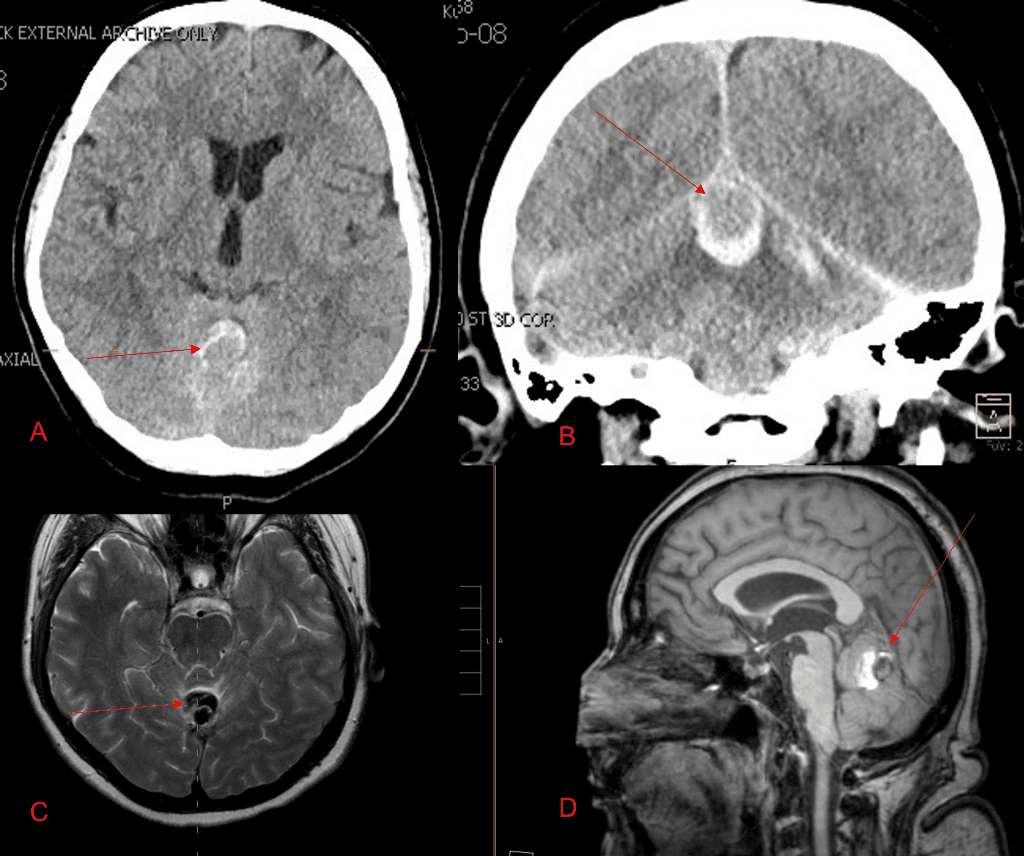

Figure 3. Right ECA AP and Lateral angiograms Pre (A and B) and Post NBCA embolization (C and D) Demonstrate near complete obliteration of right Occipital and Middle Meningeal Artery Fistulas

Figure 4. Left ECA AP and Lateral angiograms Pre (A and B) and Post NBCA embolization (C and D) Demonstrate near complete obliteration of Left Occipital Artery Fistulas.

Embolization was successful at immediately reducing the pressure into the Aneurysmal Varix with greater than 90% reduction in A-V shunts. After an intensive period of critical care monitoring and care for her initial brain hemorrhage, she made a near complete recovery with mild intermittent left sided paresthesias and generalized deconditioning. After receiving inpatient and outpatient Acute Rehabilitation, Physical, and Occupational therapy, she completely recovered all of her Activities of Daily Living (ADLs) at 3 months and achieved an modified Rankin Scale (mRS) of 0. On follow-up angiography, small residual low flow A-V shunts were identified and targeted for Gamma Knife Radiosurgery (Figure 5 and 6).